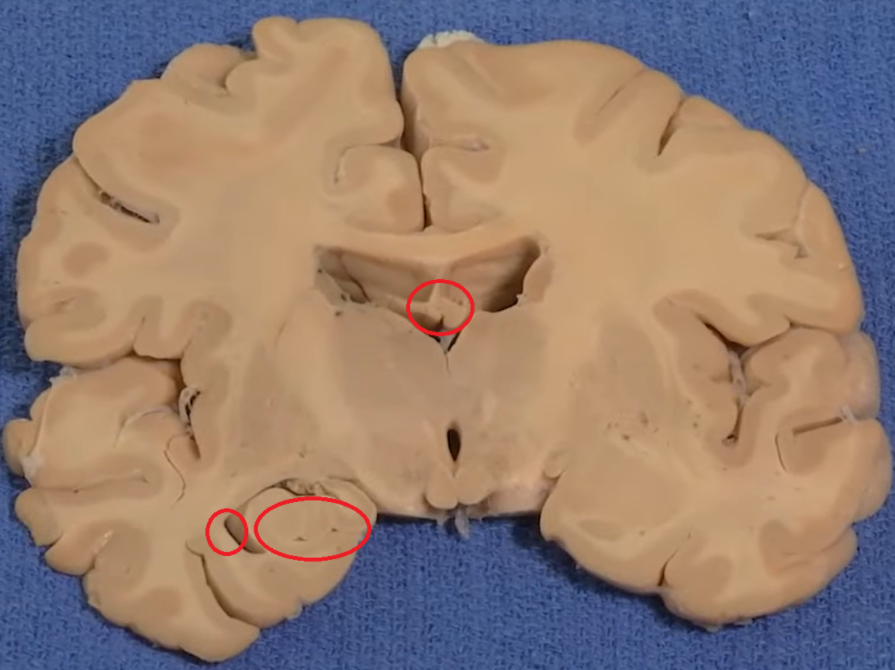

Thalamus (pink) and hypothalamus (yellow): their medial surfaces border the third ventricle (blue).

Overlaying the green cingulate and parahippocampal gyri with the purple hippocampus highlights the limbic lobe. Yellow = fornix. Brownish pink = hypothalamus

The purple hippocampus is visualized tracing the ventricular system (turquoise).